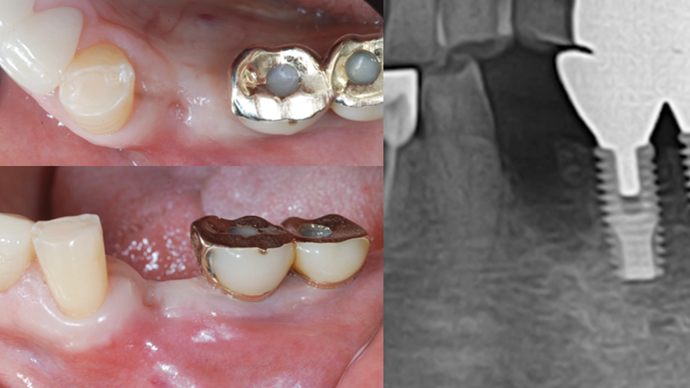

Clinical case: : Immediate loading of lower molars using R2Gate prefabricated 3D-printed provisional restoration

- Courtesy of Dr. Sam Omar, Egypt -

Keywords

Dr.Sam Omar, immediate loading, digital guided surgery, digital ONE-DAY implant, maxillary anterior, #21, guided surgery, immediate loading, AnyRidge, R2GATE, Mega ISQ, MEG Torq, R2GATE Full Surgical Kit

Products:

implant system, R2GATE Guide, R2GATE surgical kit (AnyRidge), Mega ISQ

“ONE-DAY implant, one-day smile

”